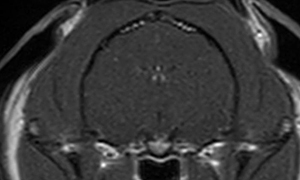

<MRIって?>

MRIは磁気共鳴画像診断とも呼び、強力な磁力と電波により臓器や血管などを画像化する検査。

MRI検査・脳脊髄検査を実施したが、脳に発作を起こすような異常は認められなかった。